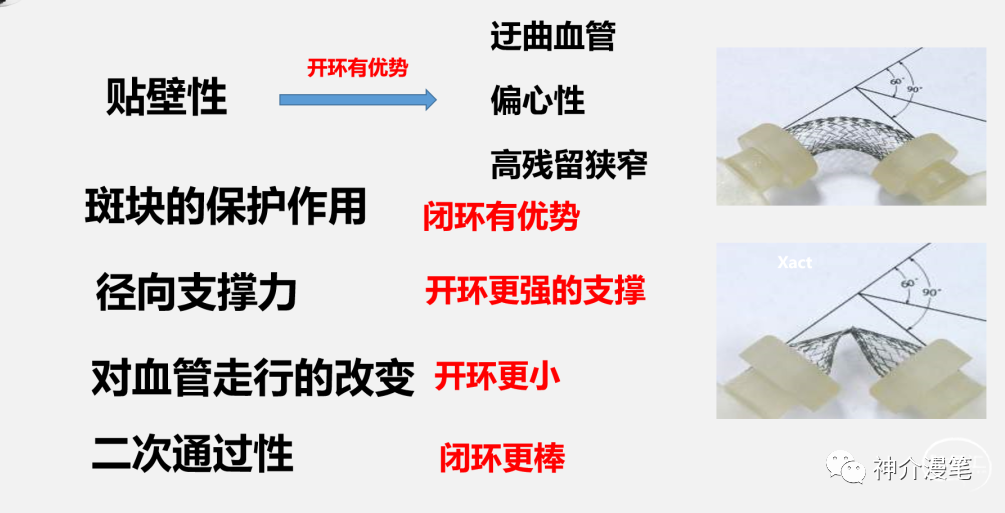

基于前面啰七八嗦的介绍,那么更适合不同支架的应用场景是什么样子的呢?声明一点的是纯学术探讨,没有任何不良导向和利益导向

对于血管走形迂曲,管径差异较大,偏心性狭窄。预期支架贴壁困难时,首选开环支架。因为其独立支架单元的结构,更容易贴壁。下图所示,管径差异较大时,左图的闭环支架在狭窄局部贴壁不良,而右图的开环则有更好的贴壁性。

从其他角度讲,开环支架对于血管走形的改变会较小,能大体顺应血管走行。而闭环支架更多的趋势是趋于一根直棒棒,对于迂曲血管走行相对改变较大。其实很多情况下,我们并不希望血管的走行被改变过大。下图为闭环和开环释放后对血管走行改变的模式图,左图为闭环释放后血管的形态预测,整体的走行改变还是会大一些。

闭环支架更大的优势来源于更密更为紧凑的网孔设计,对于提高局部金属覆盖率,保护斑块脱落,特别是溃疡斑块,软斑块等有其独特的优势。此外对于串联病变,闭环支架具备更好的二次通过性,内壁更为光滑,很少出现导管通过困难等问题。因此对于对于串联病变,夹层修复,编织闭环更具优势。